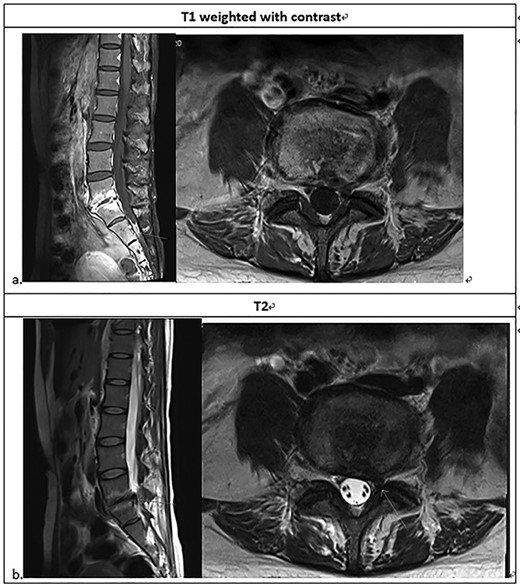

Lumbosacral MRI ~3 weeks after the intervention; less enhancement compared to the previous MRI at the L5-S1 intervertebral disc with adjacent endplates, consistent with spondylodiscitis; less compression of the left S1 nerve root.

Follow-up MRI after 1 month of antibiotics showed little change at the L5-S1 intervertebral disc and adjacent endplates, consistent with partially treated spondylodiscitis. There was also less compression of the left S1 nerve root (Fig. 3).